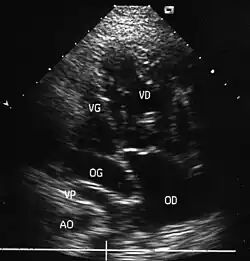

- La coupe parasternale gauche grand axe : elle montre que le vaisseau issu du ventricule gauche (le plus postérieur) se dirige anormalement vers l'arrière et se bifurque précocement. C'est donc le tronc pulmonaire et non l'aorte comme normalement.